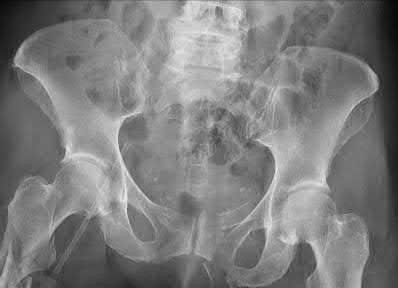

A 45-year-old man is involved in a high-speed motor vehicle collision. The AP pelvis radiograph demonstrates an acetabular fracture. According to the Letournel classification, which of the following radiographic lines is typically disrupted in an isolated transverse acetabular fracture?

A transverse acetabular fracture is an elementary fracture pattern that involves a single fracture line crossing the acetabulum horizontally. Because it bisects both the anterior and posterior columns of the acetabulum, it disrupts both the iliopectineal line (anterior column marker) and the ilioischial line (posterior column marker) on a standard AP pelvis radiograph.